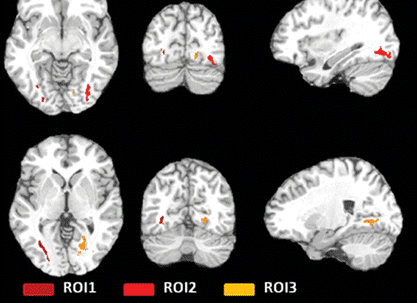

We prepare our residents for their careers as physicians with a training that emphasizes hands-on teaching and graded independence. Our Diagnostic Radiology Residents learn to dictate cases independently through apprentice-style teaching at the workstation and an extensive didactic teaching curriculum, while our Integrated Interventional Radiology Residents gain valuable clinical experience by practicing in multiple environments and managing patient care. Each resident sees a high volume of cases, including severe cases in our NCI Cancer Center and Liver Transplant Program. Specialty collaboration, direct feedback, collegiality and research opportunities allow every resident to maximize their potential.

On the East Campus, the Jack D. Weiler Hospital is the central hub where Montefiore Einstein Radiology Residents experience hands-on training in an academic community hospital setting. The hospital’s location at the Albert Einstein College of Medicine Campus allows fellows to work directly with faculty and develop independence through hands-on-training. Weiler is also home to the Albert Einstein Cancer Center, which provides extensive case material for clinical cases and highlights multiple interdisciplinary conferences. Residents work directly with faculty on the Interventional Radiology (IR) service and take independent calls as senior residents from Einstein, enhancing their learning and independent clinical practice. The East Campus is also home to the PET Imaging Center, a dedicated Nuclear Medicine outpatient facility, and the nearby Comprehensive Breast Cancer Care Center.